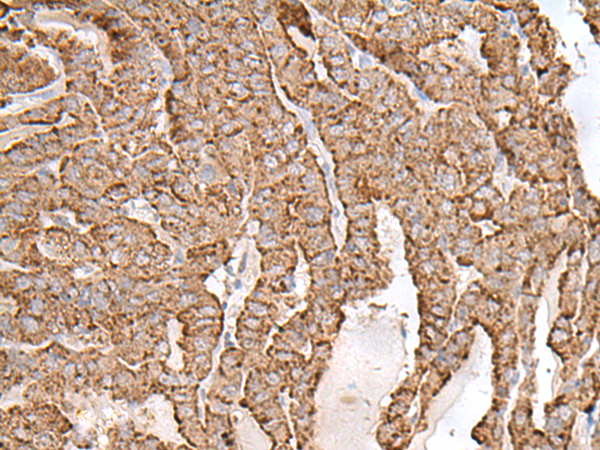

IHC positive control: |

Human thyroid cancer |